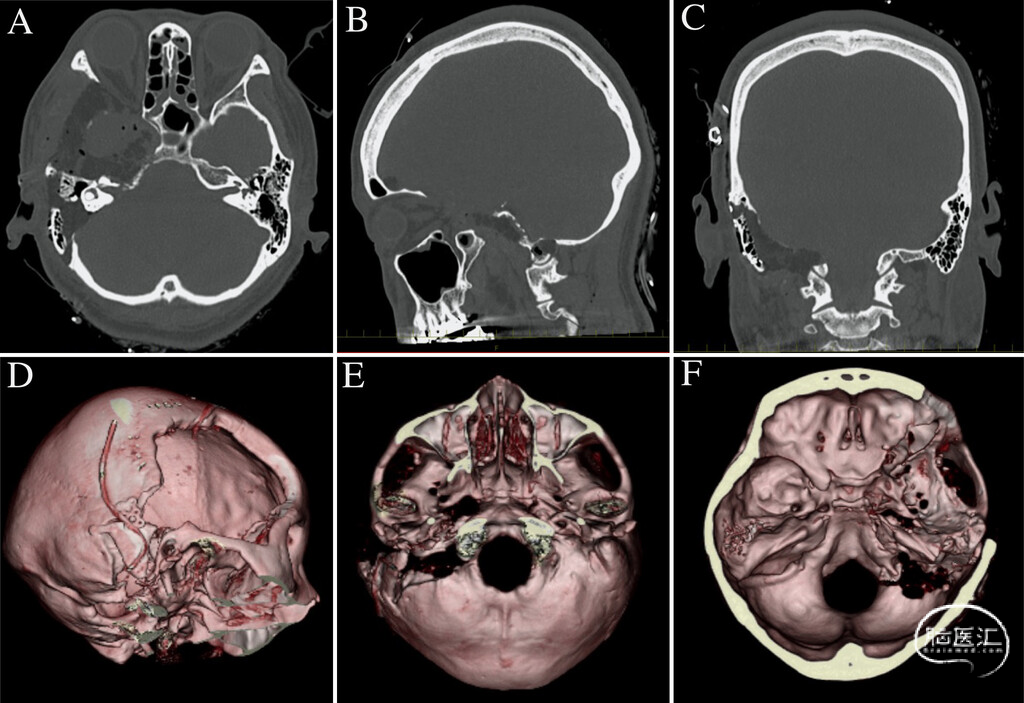

图4:A-C:术后非增强CT图像,证实减压充分、无出血。D-F:术后三维骨重建图像,显示颅底磨骨范围。

7.关颅:用自体脂肪填塞肿瘤切除后的瘤腔,使用钛板重建乳突外侧骨缺损。因之前感染已去除骨瓣,额颞部骨缺损未行颅骨成形术。放置2根引流管,按标准逐层缝合关闭切口。尽管约95%的肿瘤已被切除,但为安全起见,刻意保留了紧贴颈内动脉前壁的一薄层肿瘤。术中第Ⅴ、Ⅶ、Ⅷ、Ⅸ、Ⅹ、Ⅺ对颅神经均得到完整保留,全程神经电生理监测稳定,未发生意外出血及神经功能恶化。因手术时间较长、存在颅神经并发症风险,术后患者转入重症监护室,保留气管插管过夜。术后CT检查未见出血(图4),腰大池引流管于术后早期拔除。